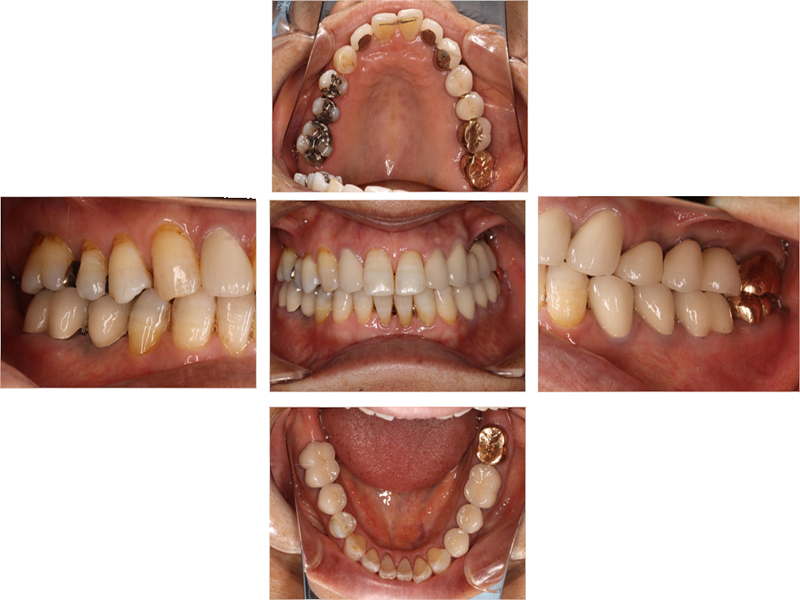

▼ ケース5 下顎前歯部叢生症例

初診時口腔内写真

初診時X線写真

治療終了時

before

after